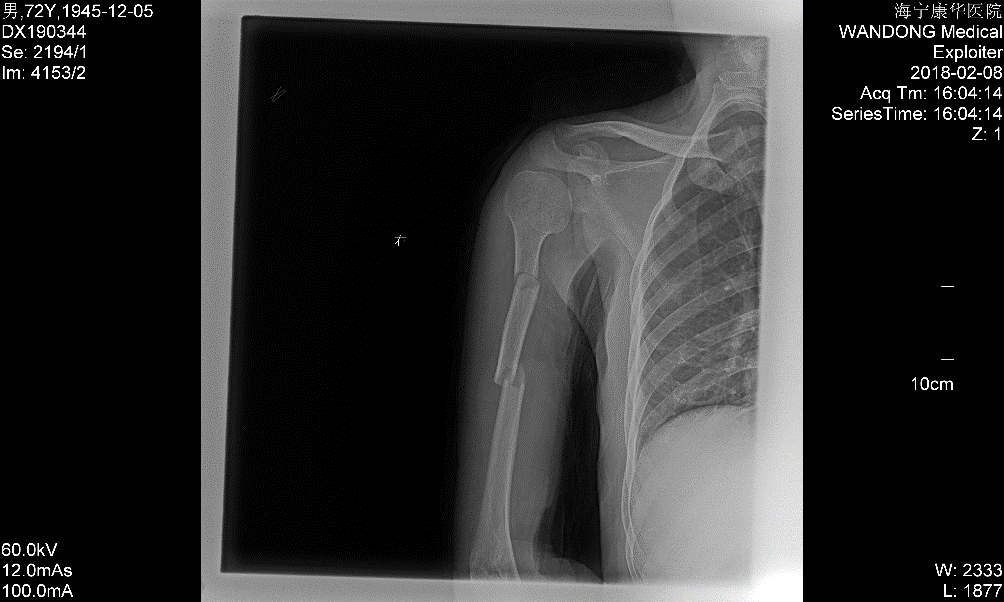

“片子上看属于右肱骨多段骨折,也就是这里和这里,两个地方都骨折了”,陈主任细致地解释着,“一般应该行切开内固定手术,但多段骨折手术皮肤切口较长,剥离广,血供破坏多,骨头愈合也困难。由于大伯右手臂本身有小儿麻痹症,上肢较正常略细,考虑再三,建议试行手法复位夹板外固定治疗,经过与患者及家属的沟通,其欣然接受保守治疗,能不开刀最好。”

一周后,X片显示骨折位置同前,并没有出现移位情况,李先生跟李大伯都面露喜色,陈主任也略略松了口气,又重新为李大伯的外固定进行了调整加固。